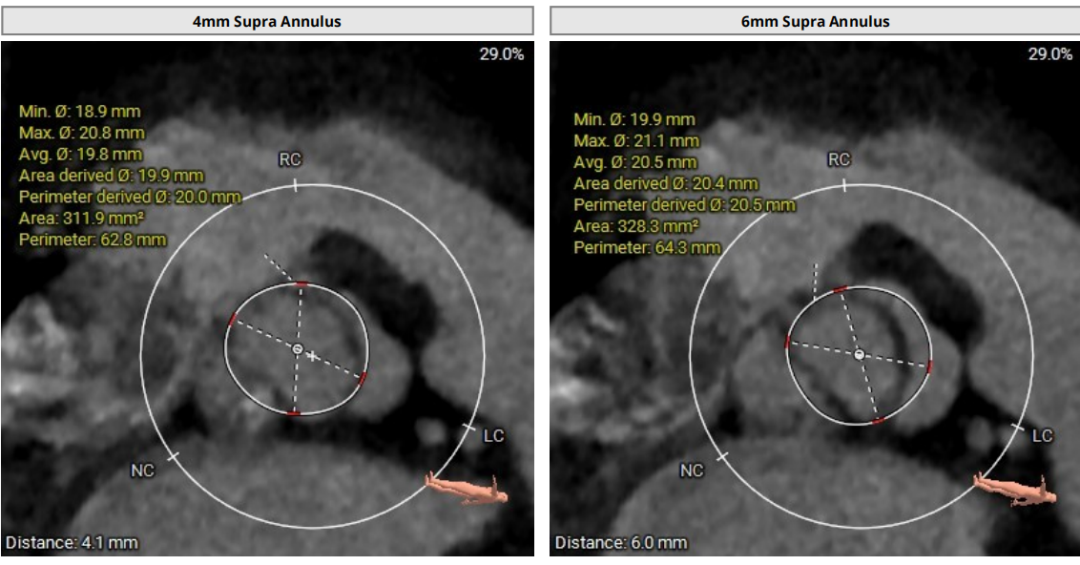

术前CT评估

瓣上分析

3) 根据瓣环瓣上测量结果,综合评定不预扩张,预装TaurusElite26瓣膜;沛嘉2代输送器非常柔顺,有利于跨过扭曲的主动脉弓部;

4) 释放采用左右重合体位,瓣下2mm释放,结合多体位术中进一步评估瓣膜深度;